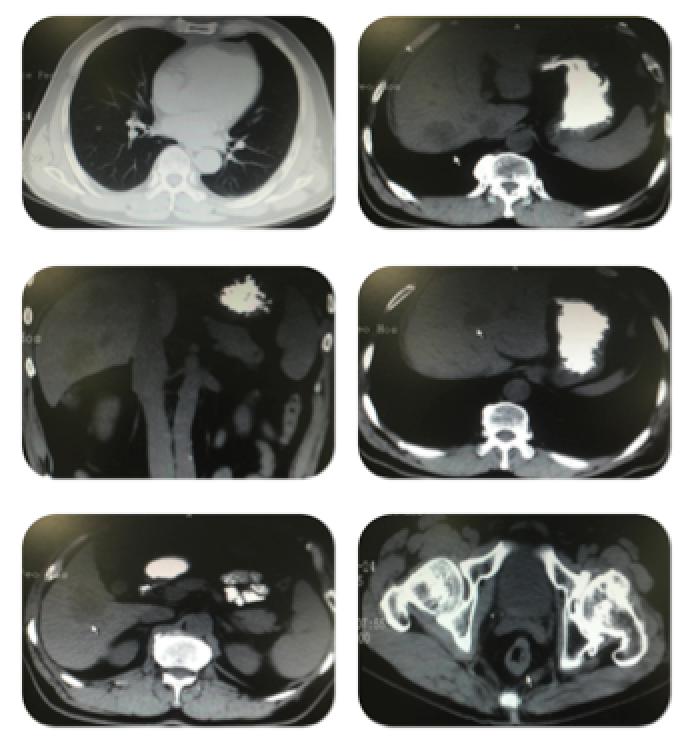

疾病进展时影像学图片:

胸部+上下腹部+盆腔CT示:1.右肺斜裂走行区小结节2.肝脏多发低密度影,结合病史考虑转移瘤 3.胰腺周围淋巴结轻度肿大;以上病变较前(2015-11-4)肝内病变较前增多、增大,4.直肠壁不规则增厚,结合病史考虑直肠癌,较前片(2015-8-5)直肠壁较前稍好转,盆腔 淋巴结较前稍减小。余变化不著。

疾病进展时生物标志物:CEA:>60ng/ml CA19-9:46.63U/ml